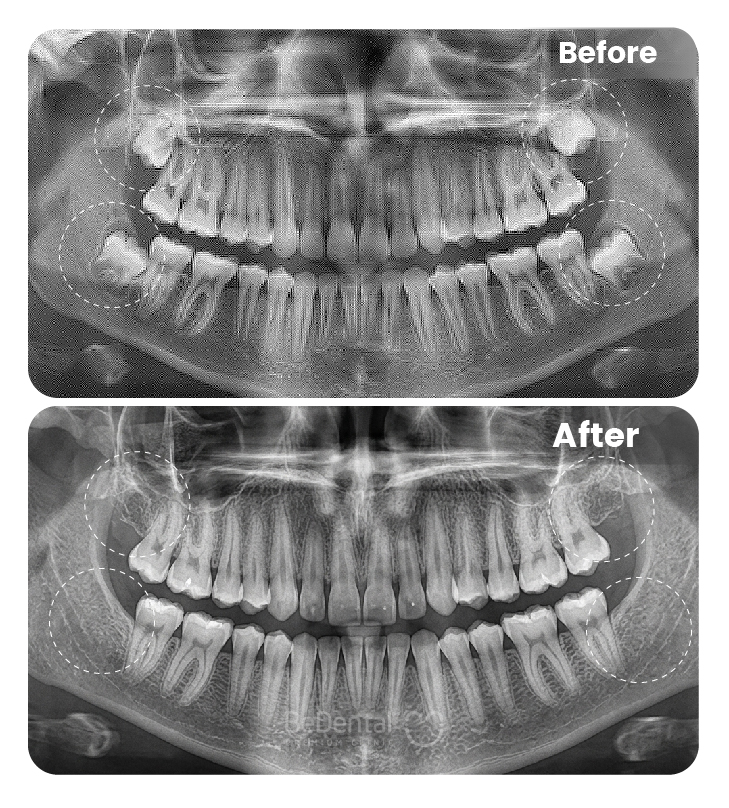

Nhổ răng khôn là thủ thuật nha khoa nhằm loại bỏ răng số 8 mọc lệch, mọc ngầm hoặc gây đau nhức, viêm nhiễm. Với sự hỗ trợ của công nghệ hiện đại và gây tê an toàn, quá trình nhổ răng diễn ra nhanh chóng, hạn chế đau, giúp ngăn ngừa biến chứng và bảo vệ sức khỏe răng miệng lâu dài.